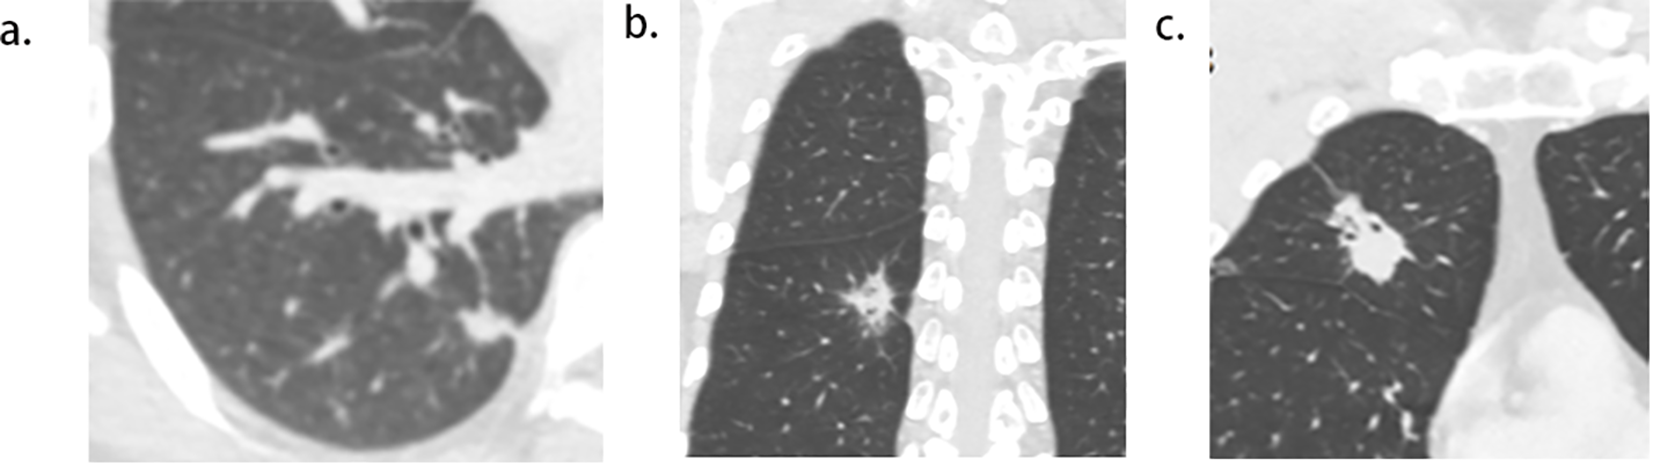

Figure 4

Pictogram of multiple pleural tags (PTs) to multiple types of pleura. (A), single PT to single pleura (costal pleura in this case). (B),multiple PTs to single pleura (costal pleura in this case). (C), multiple PTs to multiple pleura (costal pleura and fissure were involved in this case).